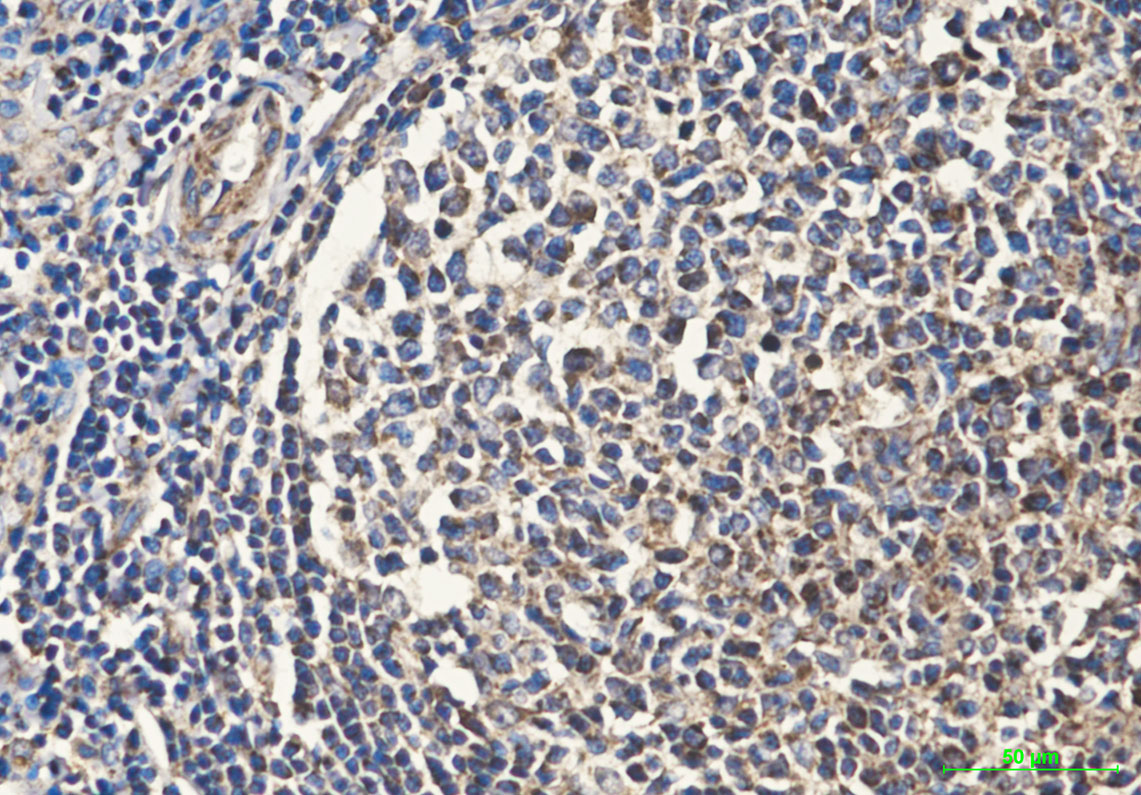

- Immunohistochemistry analysis of paraffin-embedded uman tonsil tissue using Cytochrome C antibody.High-pressure and temperature Sodium Citrate pH 6.0 was used for antigen retrieval.